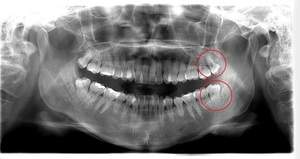

右下奥歯が痛い症例

- 抜歯前写真(レントゲン)

| 年齢 | 40代・男性 |

|---|---|

| 主訴 | 右下奥歯が痛い |

| 親知らずの生え方 | 斜めに生えている |

| 抜歯時間 | 30分 |

| 費用 | 約6,000円(保険診療、CT代含む) |

| 抜歯内容 | レントゲン上で右下の親知らずが大きく虫歯になっており、斜めに生えていることもあり患者様の希望により抜歯することとなりました。 当日は痛みがあったため抗生剤と鎮痛剤にて炎症を抑え、後日歯ぐきを切開し、抜歯を行いました。 レントゲン上でも分かるように親知らずの根が二つに分かれており根が折れてしまう可能性がありましたが、このケースでは事前にCTを撮影し、歯の位置、根の方向を確認していたため根が折れることなく抜歯ができました。 術後数日は腫れと痛みがありましたが、薬の服用で抑えることができ、1週間後の糸取りの際には痛み、腫れともになくなっていました。 |